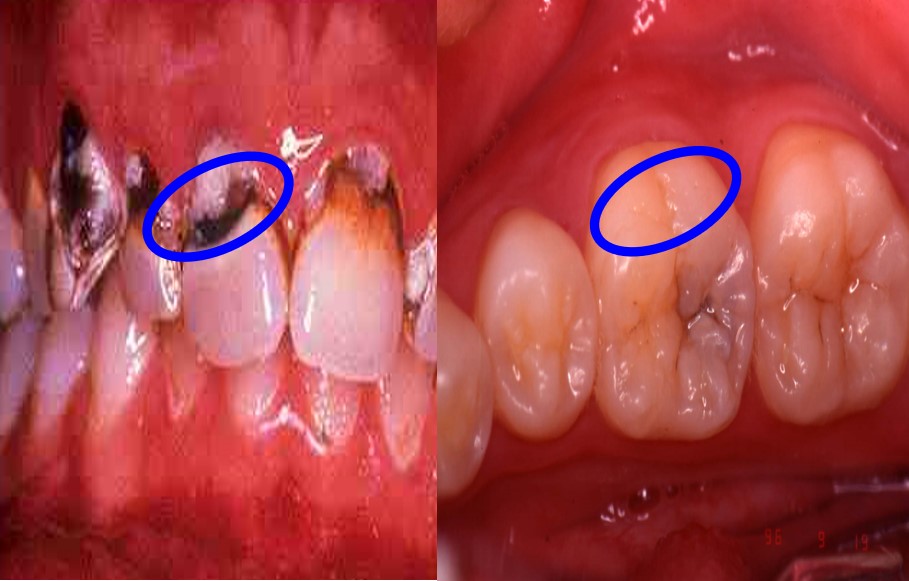

2)好发牙面及部位

★咬合面点隙窝沟(图7.1-3)>邻面接触点下方(图7.1-4)>唇颊面的近龈缘牙颈部及磨牙颊侧点隙 (图7.1-5)

图7.1-3 咬合面点隙窝沟

图7.1-4 邻面接触点下方

图7.1-5 唇颊面的近龈缘牙颈部及磨牙颊侧点隙

3)龋病发生发展的过程(图7.1-6)

图7.1-6 龋病发生发展过程